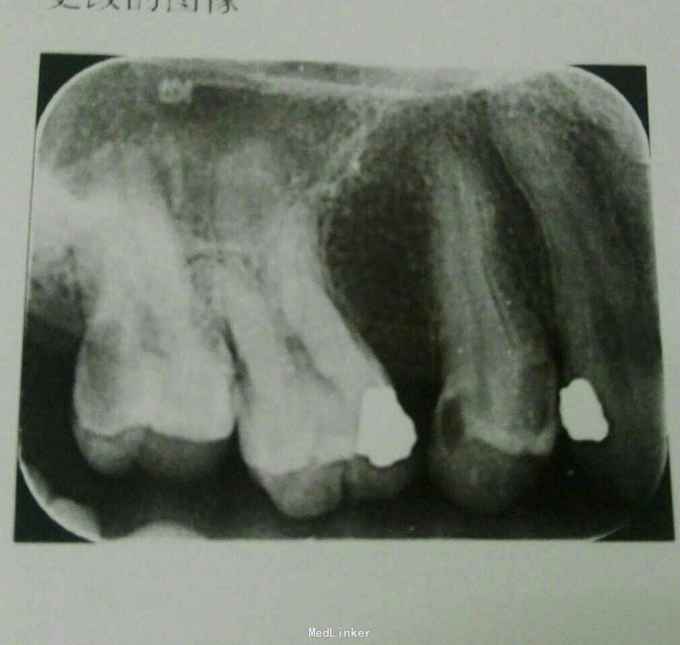

检查:17远中牙冠大面积缺损,进髓,探-,冷诊不适,叩+,无明显松动,牙龈未见明显异常 x线:17远中牙冠大面积低密度透射影,进髓,牙周膜宽度基本正常,根尖未见明显异常

诊断:17牙髓坏死 治疗计划:17根管治疗 处置:17开髓,去腐,揭顶,大量交替冲洗,探及颊腭侧两个根管口,沿牙冠中央颊舌向对称分布,未见第三个根管口,置CP棉球,氧化锌暂封 一周后复诊:17去除暂封,测根长,B=18mm,P=19mm,K锉加EDTA扩大根管,发现B根管口远中间隔1mm处有一个疑似根管口,C锉探入,测得根长17.5mm,扩大MB,DB至30#,P扩大至40#,冲洗,置CP棉球,氧化锌暂封 一周后复诊:试主尖,冷侧压充填,氧化锌暂封,观察一周后建议全冠修复